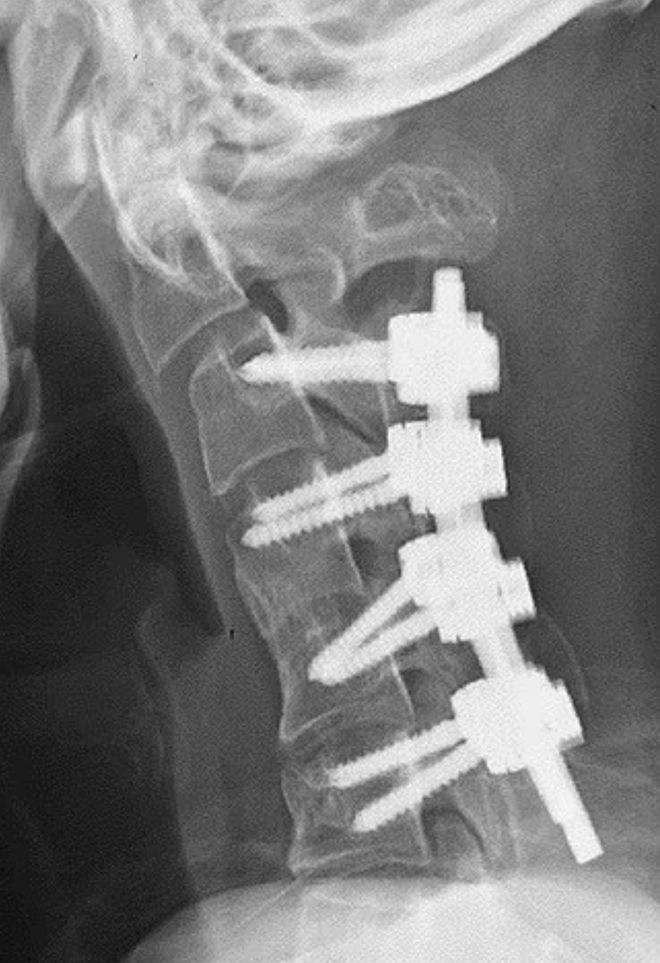

医护人员最初尝试用颈圈来纠正该患者的“下垂头综合征”,但由于其反映佩戴设备时感到麻木,因此停止了这种治疗。医生后来选择了一系列外科手术,首先切除了患者的小段椎骨和颈部的一些疤痕状组织,然后将一系列螺钉和金属棒插入他的颈骨以矫正姿势。

手术六个月后,患者能够轻松地将头部保持水平位置。在一年后的医院随访中,该男子表示,术后他抬头和吞咽困难的问题没有再出现。